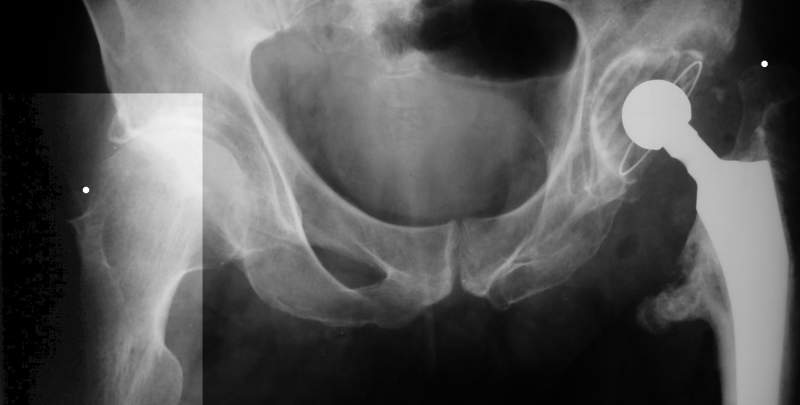

Еще пара фото, ситуация несколько иная, задачи те же, открытое вправление застарелого вывиха в 2002, молодой возраст. Сейчас госпитализирована для эндопротезирования.

А за счет чего такое укорочение? По снимку не видно соответствующего дефекта. Ну плюс приводящая контрактура - но все равно как-то уж больно много. Может, сделать снимки и таза обзорный с обоими проксимальными отделами бедра, и коенный суставов с приложенной линейкой какой?

Невозможно не согласиться с Анатолием, чтобы заниматься адекватным планированием как минимум прямая проекция таза должна быть сделана, как

максимум для оценки состояния мышц( насколько реально возможно низвести бедро) прямая проекция таза с тракцией за больную ногу.

I agree with Dr Eid's comments. The origin of the 8 cm leg length difference is a puzzle. Is this a clinical measurement? In that case contracture of the joint might affect the measurement. Can we see an AP pelvis to include both hip joints (including a calibration object with a known length) so that the difference in leg lengths that can be ascribed to the hip deformity and bony reabsorption can be measured. This sort of xray will help with templating for the TJR also. I would be very tempted to do a one stage procedure and accept some shortening. Shoe lifts should take care of a 3-4 cm difference.

До травмы проблем с ногой не было. Укорочения, болей и т.п. не отмечал. Сегодня перемерял укорочение - меньше 7 см намерять не

По уровню малых вертелов (с учетом рентгеновского увеличения) получается 5 см. Клинически ногу низвести путем тракции невозможно. Из движений - сгибание до 40*, остальные движения "символические".

Ортопедическое укорочение пострадавшей ноги может быть и 7, и 10 см. за счет контрактур в тазобедренном суставе, а вот истинное укорочение, судя по представленным рентгенограммам, вряд ли больше 4 см.

Больного прооперировали на прошлой неделе (цементный протез, цемент с гентамицином). Использовали задне-боковой доступ. В области перелома подвижности практически не было, так что тему сообщения уместно заменить на "неправильно сросшаяся шейка". И в головке, и во впадине

были значительные дегенеративные изменения, так что ни биполяр, ни остеосинтез тут неуместны (хотя это предлагали в ortopod'е). После релиза удлинили ногу на 3 см. Дальше удлинять побоялись из-за

натяжения седалищного нерва, хотя в принципе можно было бы еще 15-20 мм нарастить. По послеоперационной рентгенограмме анатомическое укорочение порядка 15 мм. Клинически при ходьбе - 4 см, но это за счет перекоса таза.

The patient underwent cemented THR on last week. Postero-lateral approach was used. There was only minimal motion at the fracture site and we had to cut the femoral head with oscillating saw. The femoral head was deformed with it's cartilage completely absent in some areas.

Acetabulum showed gross degenerative changes, especially in superior rim. So I think it was right choice not to do ORIF in this case. After some soft tissue release we've lengthened the leg up to 3 cm. Further lengthening was possible but we stopped at that moment due to tension of n. ischiadicus. Now patient walks with crutches. Leg length discrepancy is about 4 cm due to pelvic tilt (discrepancy on post-op x-ray is 15 mm).